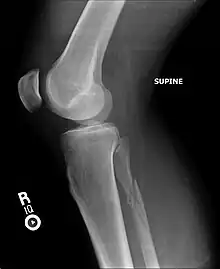

La fracture de Maisonneuve comprend une rupture du ligament deltoïde ou une fracture-avulsion horizontale de la malléole interne, associée à une longue fracture oblique de la fibula (péroné).

La fracture est associée à une déchirure de la partie distale de la syndesmose tibio-fibulaire et de la membrane interosseuse avec parfois une lésion du nerf fibulaire (nerf péronier commun ou nerf sciatique poplité externe) qui passe au niveau du col de la fibula. Cette atteinte du nerf peut entraîner une paralysie de la loge musculaire antérieure de la jambe, d’où l'impossibilité de relever le pied.